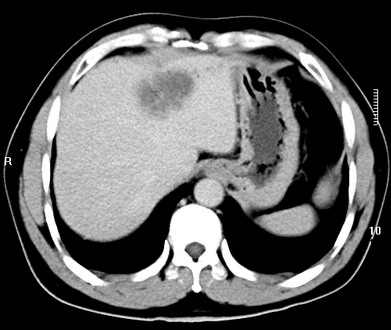

标题: CT19720:肝右叶血管瘤。肝左叶内侧段病灶考虑什么? [打印本页]

标题: CT19720:肝右叶血管瘤。肝左叶内侧段病灶考虑什么?

男,48岁,肝区不适月余,伴隐痛。

支持右叶血管瘤,左叶病灶考虑肝腺瘤。

1)不排除肝左叶肝癌。2)肝右叶血管瘤。

肝左叶炎性病变,肝癌待排。2)肝右叶血管瘤。

1.肝右叶血管瘤;2.肝左叶炎性假瘤?肝癌?建议穿刺活检.

右叶病灶典型,左叶病变慢性炎块

1、肝右叶血管瘤(典型)。

2、肝左叶病灶,强化不明显,疑炎性假瘤,建议结合临床并密切随访。

1、肝左叶炎性病变,肝癌待排。

2、肝右叶血管瘤。

肝左叶脓肿,肝癌待排。2)肝右叶血管瘤